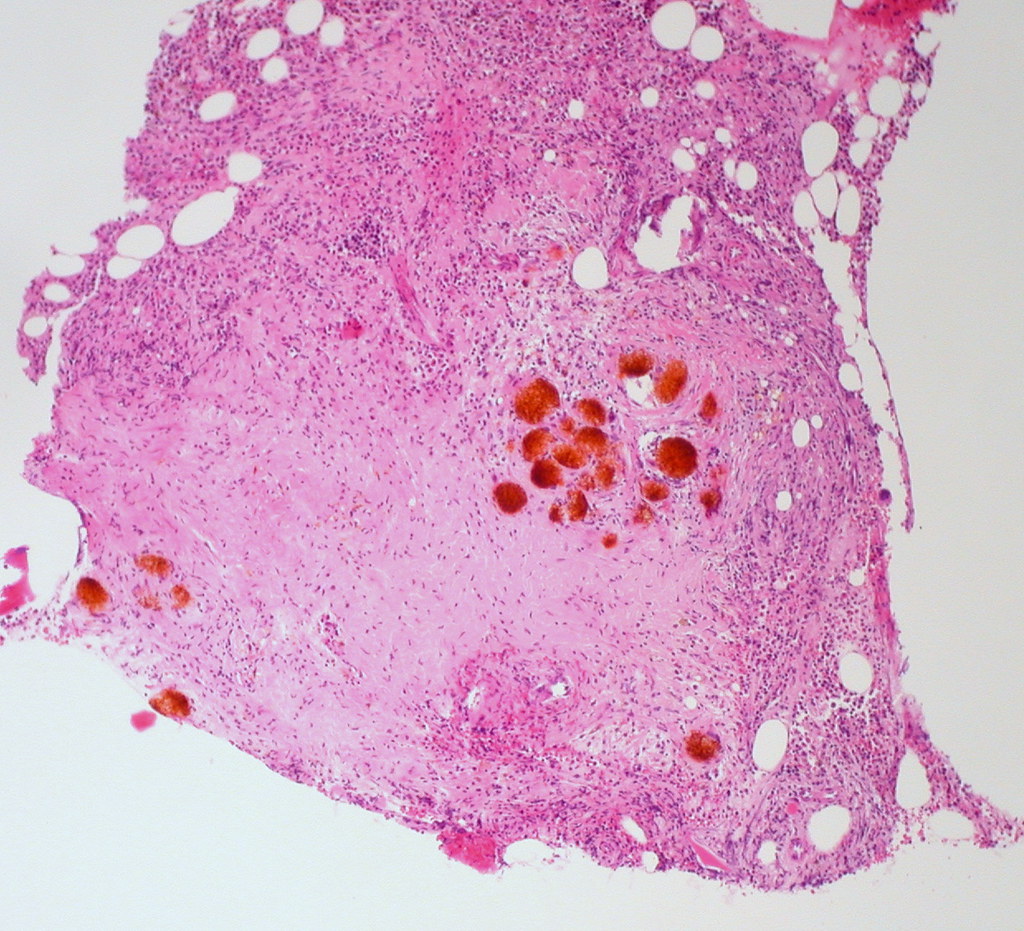

Foreign Material in Bone Marrow (H&E, 100X) Ed Uthman Flickr Gaps Between Ossified Material Are Filled With Marrow The diaphysis is the tubular shaft that runs between the proximal and distal ends of the bone. There are two types of bone: The hollow region in the diaphysis is called the. The spaces between trabeculae are often filled with bone marrow. There are two types of marrow. Consists of interconnecting rods or plates of bone. The spaces within the. Gaps Between Ossified Material Are Filled With Marrow.